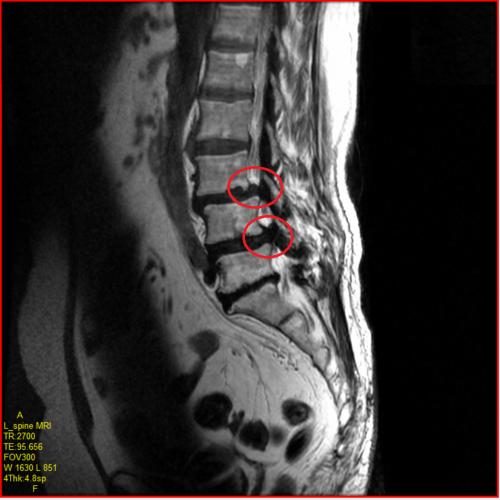

협착증 환자는 척추관을 둘러싼 그 부근 전체, 뼈, 인대, 후관절, 디스크 등이 깡그리 으로 퇴보되어 두꺼워지므로 다리로 가는 신경이 눌려서 근력이 약화되고 근육이 위축됩니다.

퇴행으로 기인해서 뼈도 골극이 자라 두꺼워지고, 후관절도 두꺼워지고, 척추관 안에 있는 인대도 두꺼워지고, 앞에 있는 디스크도 수분이 빠져 납작해지면서 척추관 공간 안을 좁게 만들고요. 이렇듯 척추관을 둘러싼 근처 전체가 다 두꺼워지고 해서 척추관이 좁아질 수밖에 없는데요.

그리고 척추관이 좁아지니까 그 가운데의 신경이 압박되어 신경성 파행, 즉 걸음을 걸으면 다리가 아픈 증상이 나타나게 됩니다.